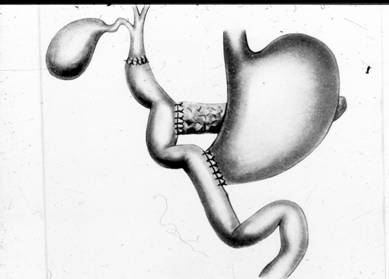

n панкреатоеюностомия:

а) продольная (Пестова-Джильсби)

б) терминальная (Дюваля)